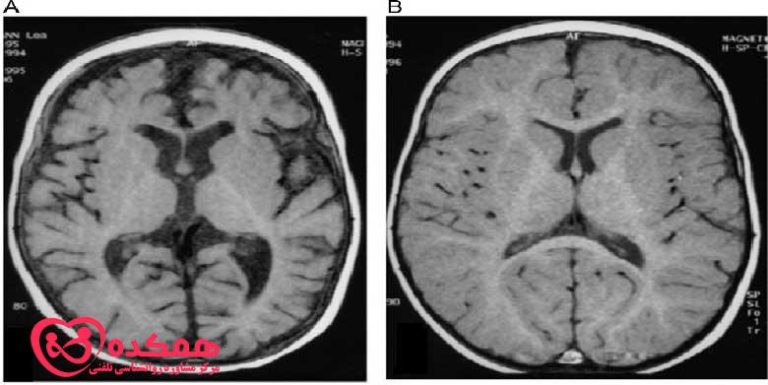

آتروفی مغزی چیست؟ علائم و 4 علل به وجود آمدن آن